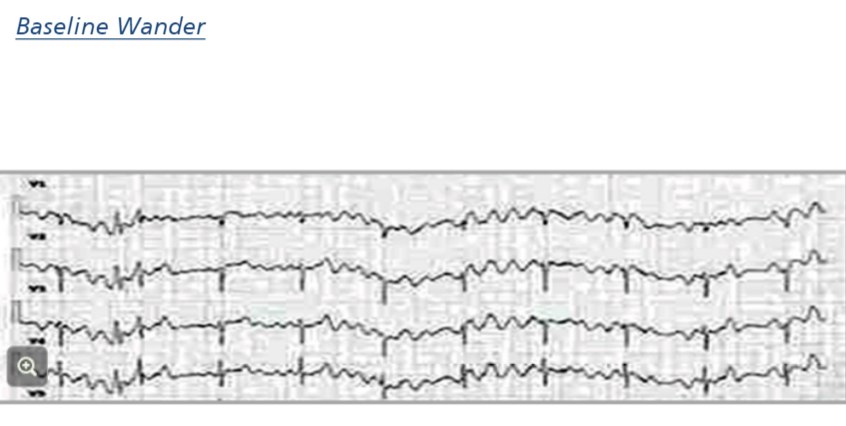

Common tracing problems are usually due to poor electrode contact Three common tracing problems are: * AC interference * Muscle tremor * Baseline wander Describe what baseline wander looks like on the ECG?

A wandering baseline is where the ECG waveform baseline is not level and instead moves like a wave Can be due to poor electrode attachment